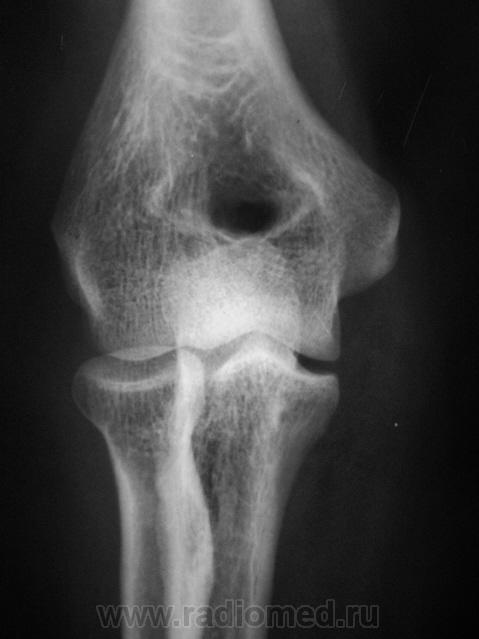

Травма. Пациент направлен на рентгенографию локтевого сустава.

Травма.    Пациент направлен на рентгенографию локтевого сустава. Исследование произведено.